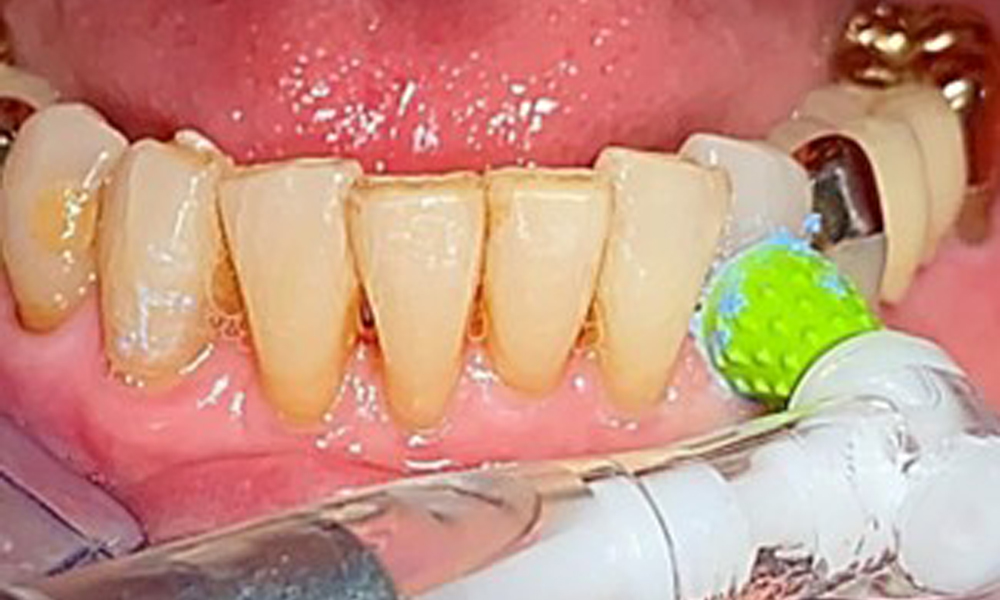

Eine Einbüschelbürste insbesondere für die Teleskope sind empfehlenswert (Abb. 8) und Interdentalbürstchen mit der passenden Größe sind der Patientin aufzuzeigen (Abb. 9). Die Patientin setzt diese Empfehlungen der häuslichen Mundhygiene seit vielen Jahren um und wird im Rahmen der unterstützenden professionellen Präventionssitzung bestärkt, dies weiterhin zu tun.

Darstellung einer Einbüschelbürste zur häuslichen Pflege für Implantate und Teleskope.

Abb. 8: Darstellung einer Einbüschelbürste zur häuslichen Pflege für Implantate und Teleskope.

Air Polishing (hier: Proxeo Aura, W&H) an einem Implantat

Abb. 12: Air Polishing (hier: Proxeo Aura, W&H) an einem Implantat

Für die Restaurationsränder und Zahnzwischenräume und Implantatoberflächen kann das Pulverstrahlgerät mit einem niedrig-abrasiven Pulver zum Einsatz zur Entfernung von Biofilm kommen (Abb. 12). Durch selektives Polieren (Abb. 13) sollte eine Glättung aller weniger sensiblen Bereiche erfolgen, da die bakterielle Wiederanhaftung reduziert wird. (9)

Selektives Polieren in Rg. 33 (hier Proxeo Twist, W&H)

Abb. 13: Selektives Polieren in Rg. 33 (hier Proxeo Twist, W&H)